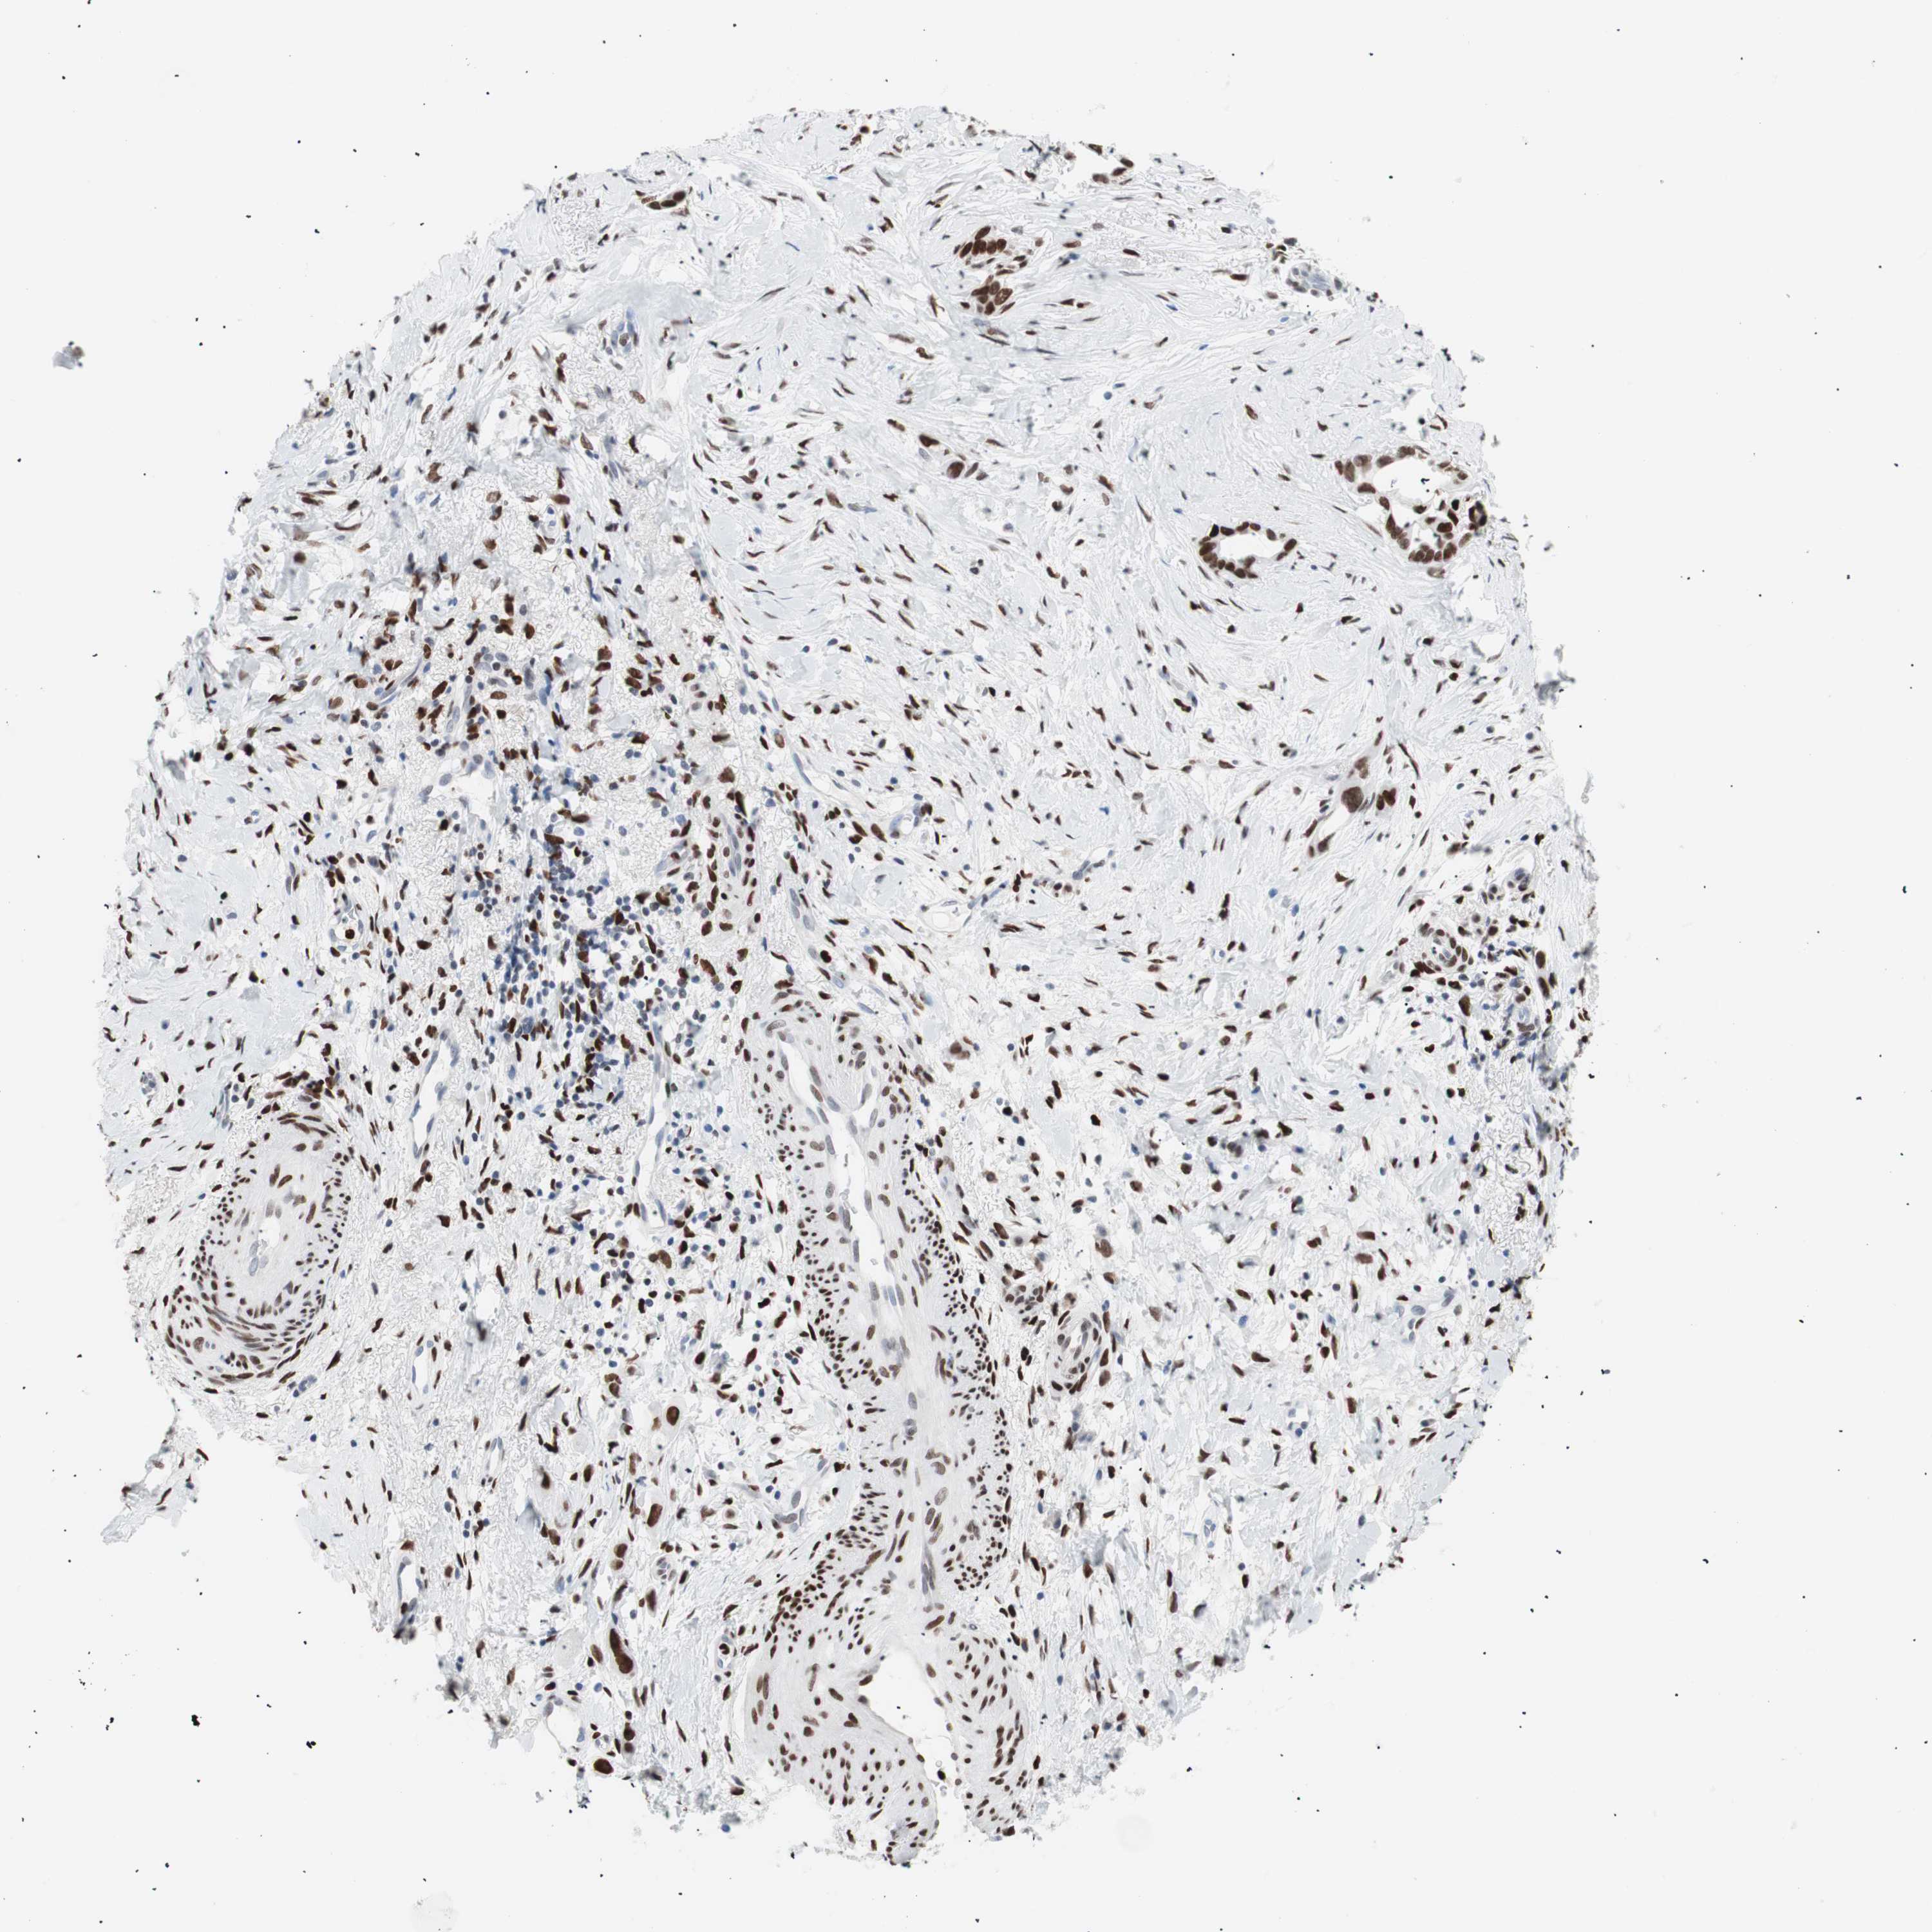

LIVER CANCER - Protein expressioni

A mouse-over function shows sample information and annotation data. Click on an image to view it in a full screen mode. Samples can be filtered based on level of antibody staining by selecting one or several of the following categories: high, medium, low and not detected. The assay and annotation is described here.

Note that samples used for immunohistochemistry by the Human Protein Atlas do not correspond to samples in the TCGA dataset.

Antibody stainingi

Antibody staining in the annotated cell types in the current human tissue is reported as not detected, low, medium, or high, based on conventional immunohistochemistry profiling in selected tissues. This score is based on the combination of the staining intensity and fraction of stained cells.

Each image is clickable and will lead to virtual microscopy that enables deeper exploration of all samples and also displays staining intensity scores, fraction scores and subcellular localization as well as patient and tissue information for each sample.

Antibody CAB004213

Staining

High

Medium

Low

Not detected

Intensity

Strong

Moderate

Weak

Negative

Quantity

>75%

75%-25%

<25%

None

Location

Nuclear

Cytoplasmic/membranous

Cytoplasmic/membranous,nuclear

Cholangiocarcinoma

Carcinoma, Hepatocellular, NOS